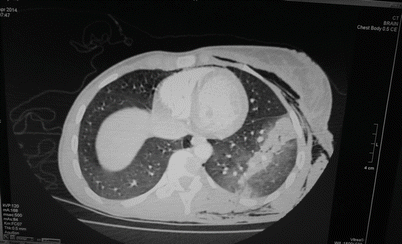

Fig. 36.4

Chest x-ray showing a high energy bullet tract causing lung contusion. There is also subcutaneous emphysema present